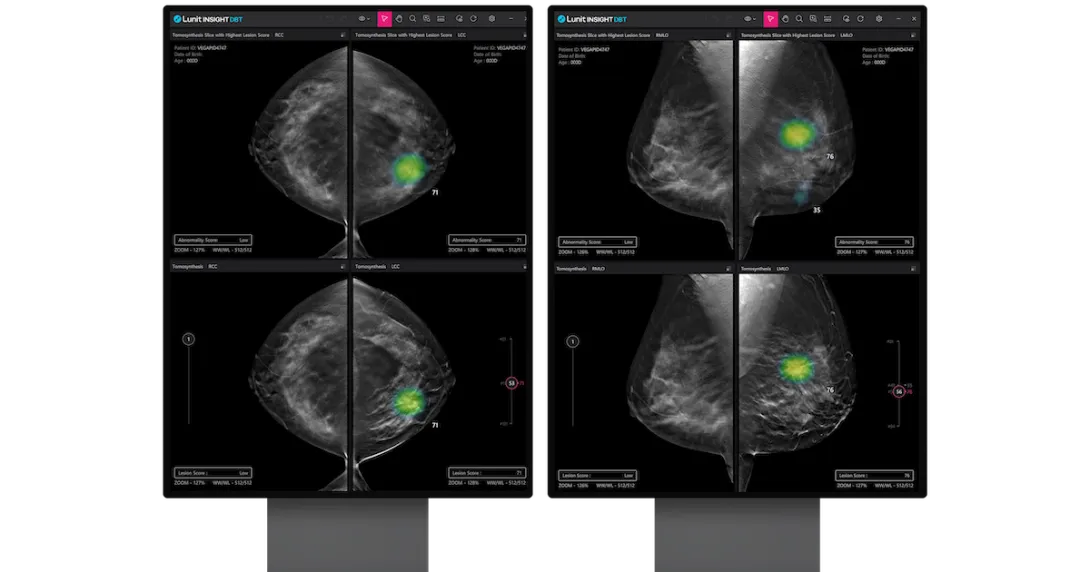

A day before it announced its significant capital raise, Lunit disclosed that it received the US FDA approval for its AI 3D Breast Tomosynthesis (DBT) solution. The 510(k) clearance for Lunit INSIGHT DBT – a solution that automatically analyses 3D DBT images to spot breast cancerfollows similar clearances for the Lunit INSIGHT CXR and MMG, which were both obtained in 2021.

The 3D DBT analysis solution has also been CE-marked under the latest Medical Device Regulation since March.